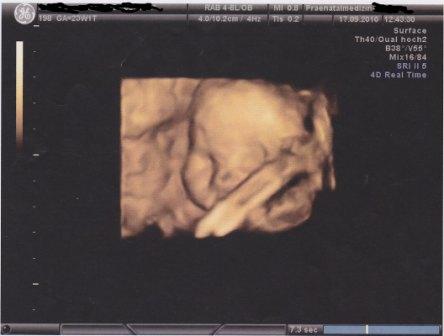

@Liebe Wuschel-Ines: Toll, das eure Termine so super verlaufen sind

ein süßes Bild von Deinem Kleinen!!!! Kann Deine Ungeduld nachvollziehen mit dem KiZi...ich wäre sicherlich nicht anders und würde am liebsten schon gleich alles fertigstellen. Aber nu´lass ma Dein Menne ran mit arbeiten, Tapeten abreißen usw. Freu mich schon jetzt auf ein tolles Foto vom fertigen KiZi!!! Viel Spaß mit dem niedlichen Hundi am Wochenende!